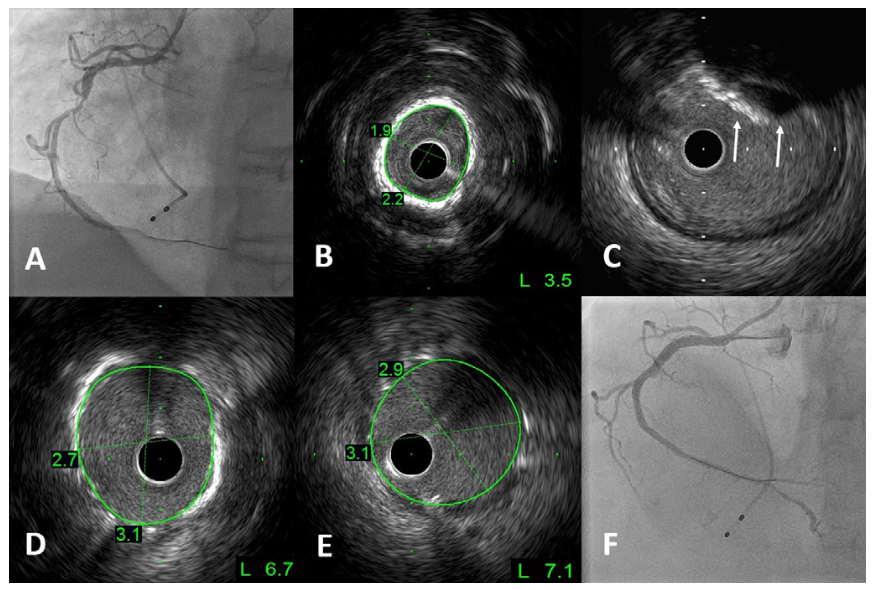

Orbital-tripsy patient #8. A 78-year-old woman with hypertension and type 2 diabetes mellitus underwent an elective coronary angiography following an abnormal computed tomography coronary angiography. The baseline angiogram showed a calcified proximal to mid LAD (Figure 4A). Baseline OFDI was acquired and showed eccentric calcification in the mid LAD (Figure 4B)and concentric calcification in the proximal LAD (Figure 4C), with maximal thickness of 0.92 mm. The workhorse wire was switched out for the ViperWire Advance to perform multiple low- (80,000 rpm) and high-speed (120,000 rpm) OA runs in the calcified segment, followed by another OFDI run to assess the calcium modification. A classic “snowman” appearance was seen in the eccentrically calcified mid LAD, a common finding after OA (Figure 4D). This unique appearance is due to the bidirectional ability of OA to ablate calcification. In the mid LAD, forward OA runs typically bias the crown toward the outer curve (diagonal side) whereas backward OA runs bias toward the inner curve (septal side). In this case, the eccentric calcification was on the inner curve, therefore, preferential ablation in this segment was achieved by predominantly backward OA runs, then advancing the crown beyond the lesion with GlideAssist mode between each run. The concentric calcification in the proximal LAD remained minimally modified by OA, therefore, a 3.0 x 12-mm IVL balloon was chosen to modify this segment. However, predilation with a 2.5 x 15-mm non-compliant balloon was required to deliver the IVL balloon, with post-stent OFDI showing calcium fractures (Figure 4E). Final angiographic result is shown in Figure 4F.